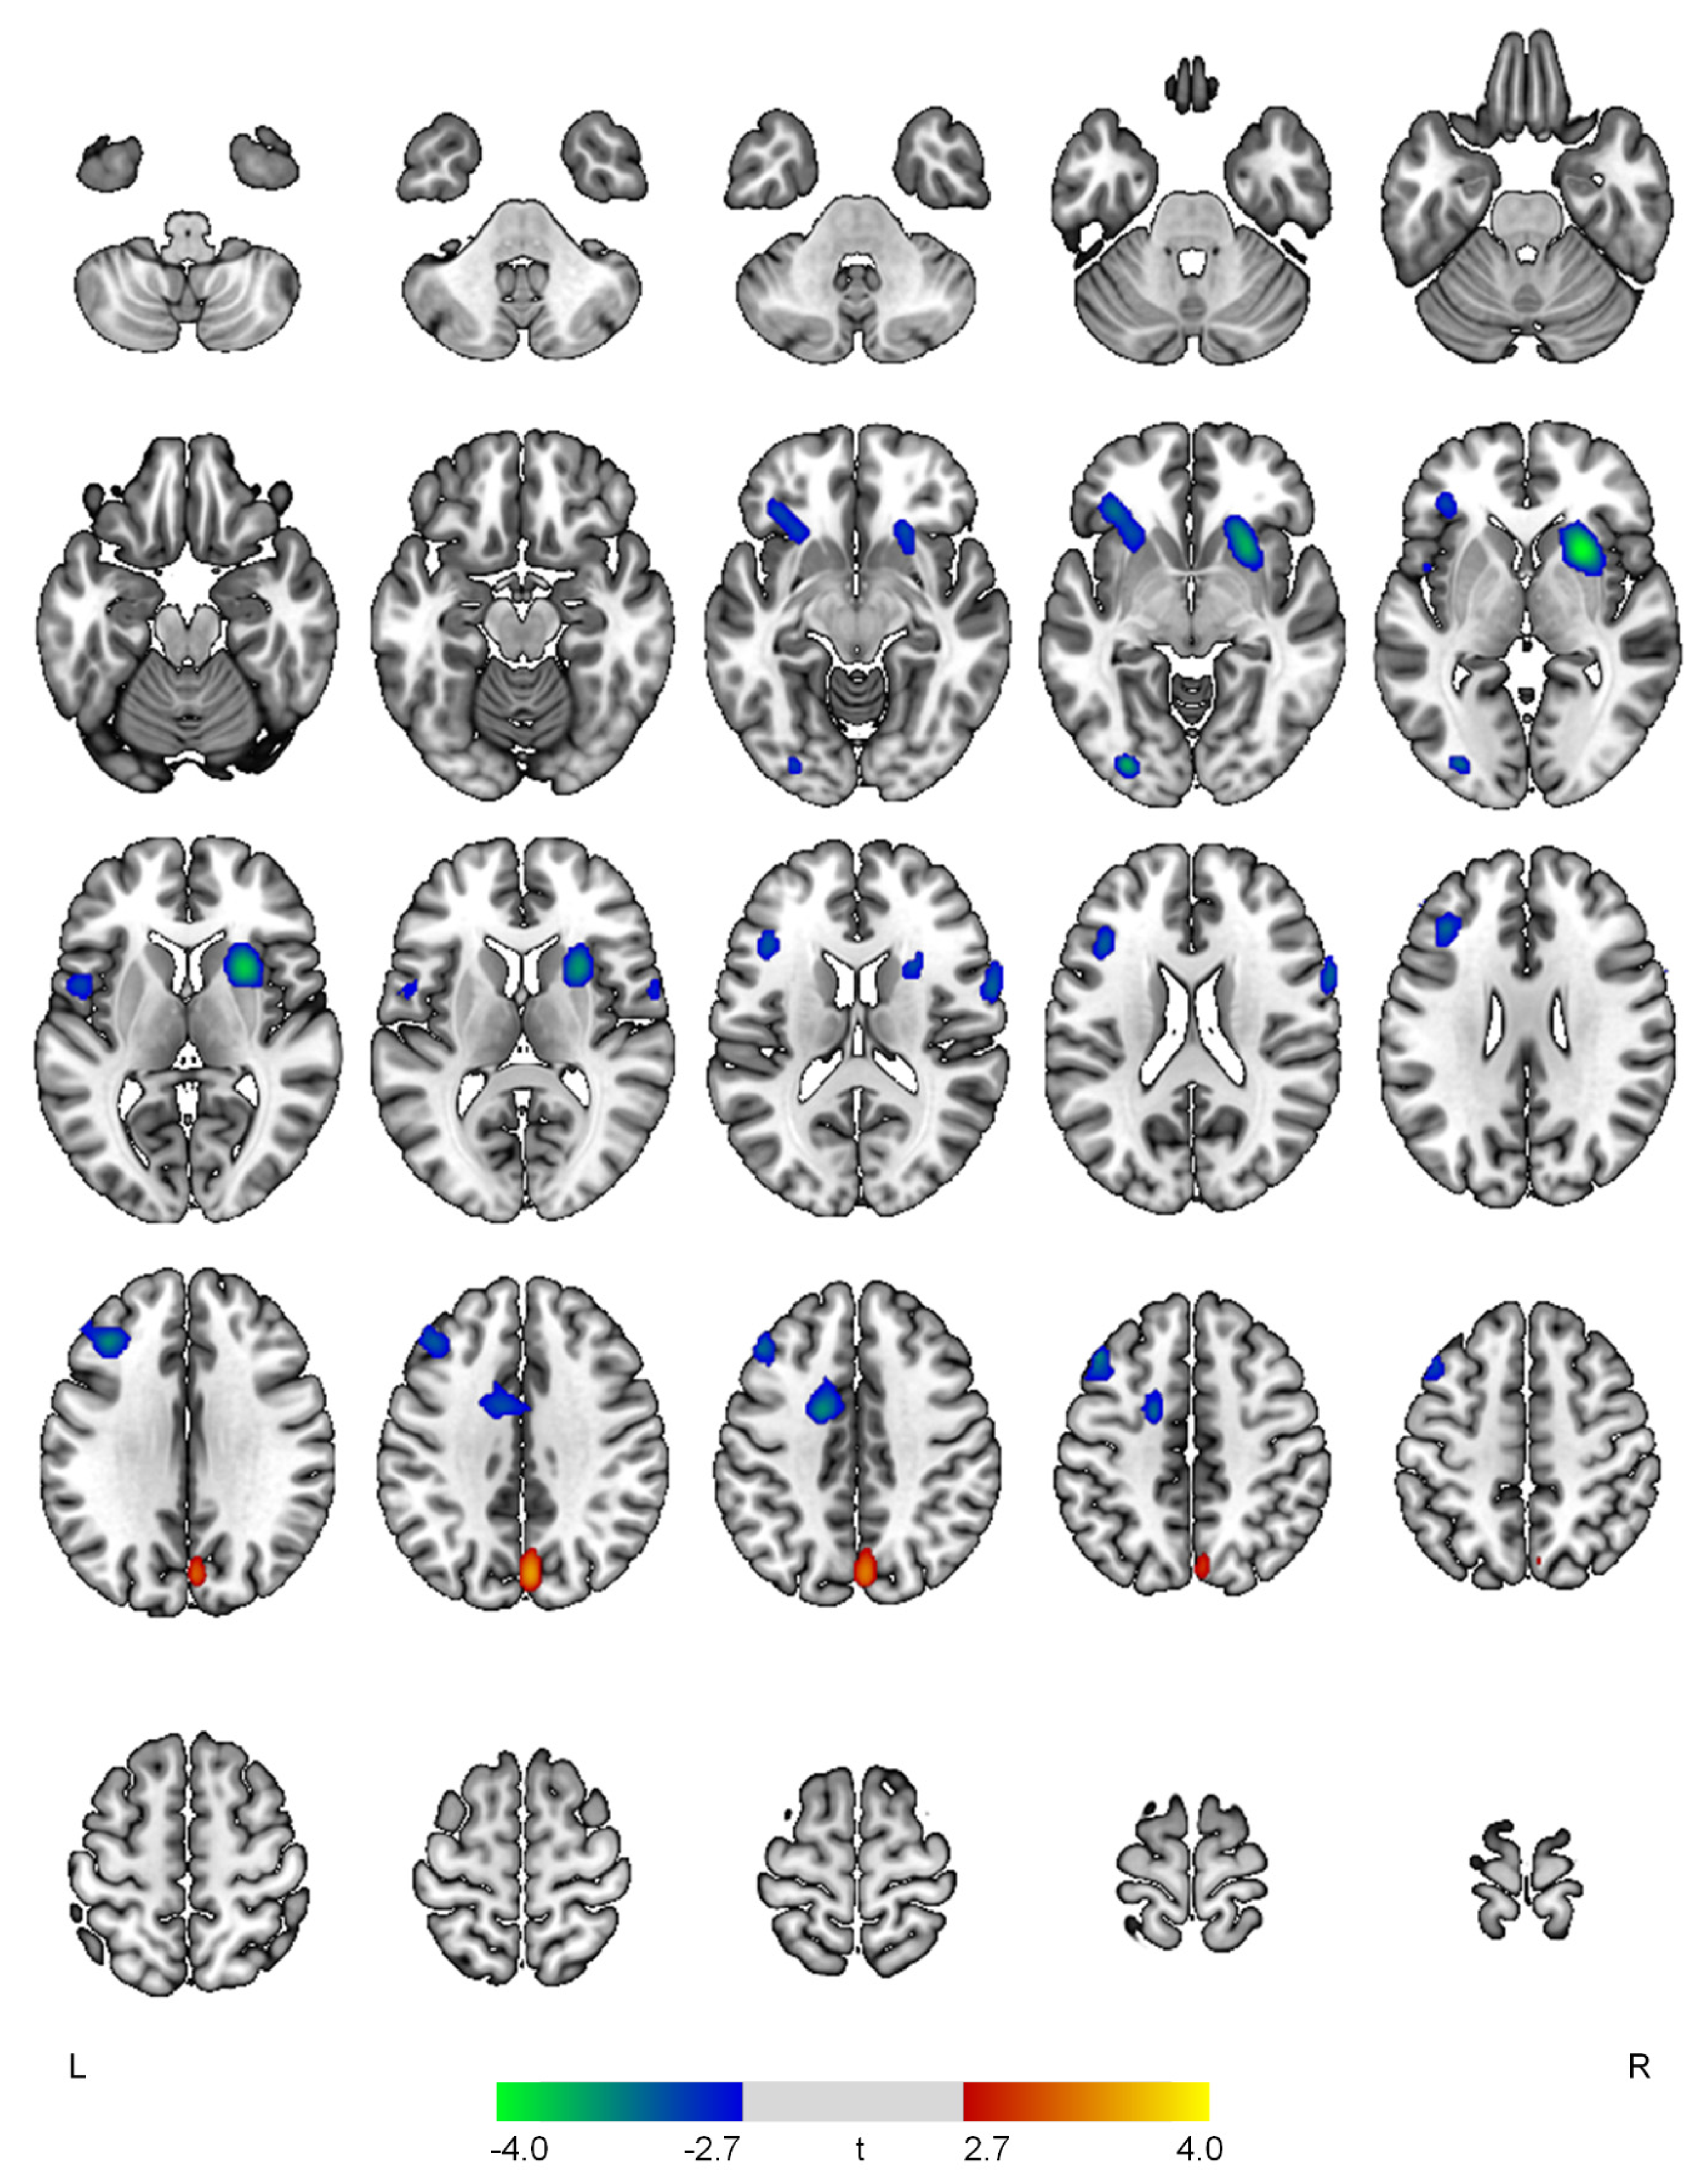

Figure 4.

Positive (red-yellow) or negative (blue-green) correlations between regional cerebral blood flow and the psychosis domain in patients with early Alzheimer’s disease. The color bar represents t values at each voxel. L—left; R—right.

The severity of the psychosis domain was positively correlated with rCBF in the right cuneus (t = 3.53, p < 0.001) and inversely associated with rCBF in the right putamen (t = 4.06, p < 0.001), left inferior occipital gyrus (t = 3.64, p < 0.001), left middle frontal gyrus (t = 3.49, p = 0.001), left anterior cingulate gyrus (t = 3.46, p = 0.001), left inferior frontal gyrus (t = 3.30, p = 0.001), right precentral gyrus (t = 3.20, p = 0.001), and left central operculum (t = 3.04, p = 0.002) (Figure 4).

In our study, AD patients with greater severity of psychosis symptoms showed decreased rCBF in the frontal, anterior cingulate, putamen, opercular, and inferior occipital regions and increased rCBF in the cuneus. In line with this, reduced rCBF, hypometabolism, and gray matter atrophy of the dorsolateral, inferior frontal, and anterior cingulate gyri have been consistently reported in AD patients with psychosis [6,8,13]. In addition, disruptions in the prefrontal-basal ganglia circuit and the cingulo-opercular network may lead to psychosis in various conditions [33,34]. Reduced cognitive control involved in the dorsolateral prefrontal cortex and impaired conflict monitoring related to the anterior cingulate gyrus may be implicated in the pathophysiology of schizophrenia [35,36]. In AD, delusions and hallucinations are known to be associated with extrapyramidal symptoms, suggesting the involvement of the basal ganglia circuits [37]. Cerebral atrophy of the occipital lobe was found in AD patients with visual hallucinations [38], which is the most typical form of hallucinations in AD [39]. The visual hallucinations in AD are known to be primarily caused by the ventral visual stream system including the lateral prefrontal cortex and occipital lobe [40].